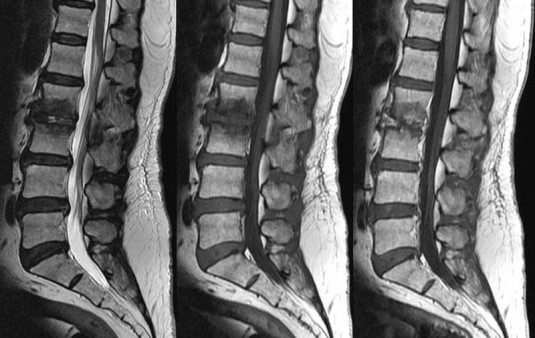

В теле здорового человека межпозвоночные диски выполняют роль амортизаторов. С возрастом, при определенных условиях, например, под воздействием тяжелых физических нагрузок, межпозвоночные диски могут выходить за пределы позвоночника — этот процесс называется протрузией. Особенно тяжело переносится пациентами протрузия поясничного отдела позвоночника, так как патологию сопровождает выраженный болевой синдром.

Диагностикой и лечением протрузий межпозвонковых дисков поясничного отдела занимаются невропатолог и физиотерапевт. Методика борьбы с этим заболеванием в каждом отдельном случае разрабатывается индивидуально после получения результатов функциональных тестов, лабораторных и аппаратных исследований.

Наиболее эффективные методы диагностики:

Врачи рекомендуют перед лечением протрузий межпозвонковых дисков поясничного отдела, особенно в сложных случаях, пройти как можно более тщательное обследование.